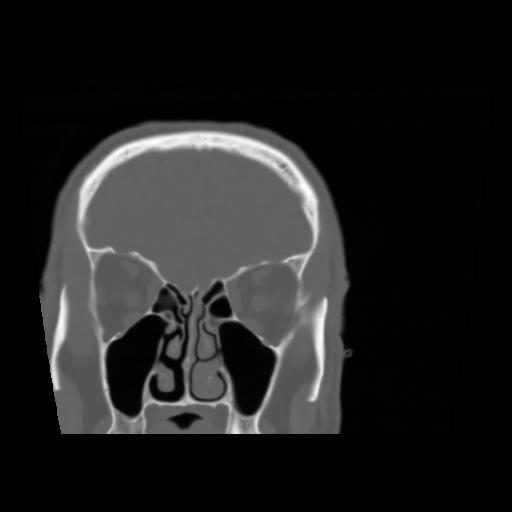

5 CEREBRO,,Coronal,3.000,CEREBRO,Coronal,